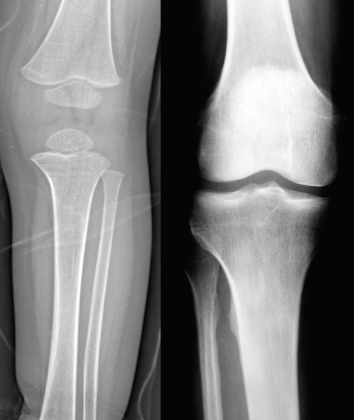

小儿:骺软骨未完全骨化,长骨分为骨干、干骺端、骨骺及骺板

成人:骨发育完全,骺与干骺端结合,只有骨干和骨端

股骨头骨骺缺血性坏死:骨骺变小、碎裂变形,颈短粗,头向外移,内侧间隙增宽。

成人股骨头缺血性坏死:股骨头变形,增骨质生硬化囊变并存;左侧间隙变窄,右侧间隙正常。关节间隙变窄,退行性骨关节病,股骨头呈磨菇头状变形